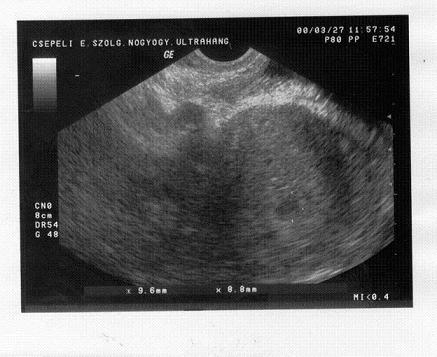

Megjöttem uh-ról, crl- 70mm NT- 1,5mm (tarkóredő) BPD 25mm.(Fejátmérő).

Teljesen egészséges, fölhangosították a szivhangot, mert szerintük ennyi szenvedés után megérdemlem.

Szóval minden rendben, egy kő megint leesett a szívemről.